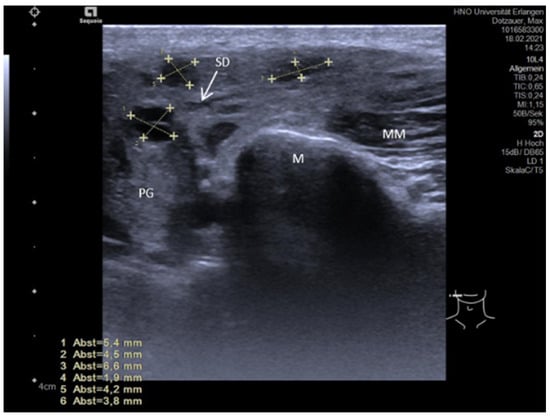

3.3.2. Obstructive Sialadenitis Caused by Sialolithiasis

3.3.3. Non-Sialolithiasis-Caused Unspecific Sialadenitis with Sialodochitis and/or Duct Stenosis with Primary or Secondary Obstruction